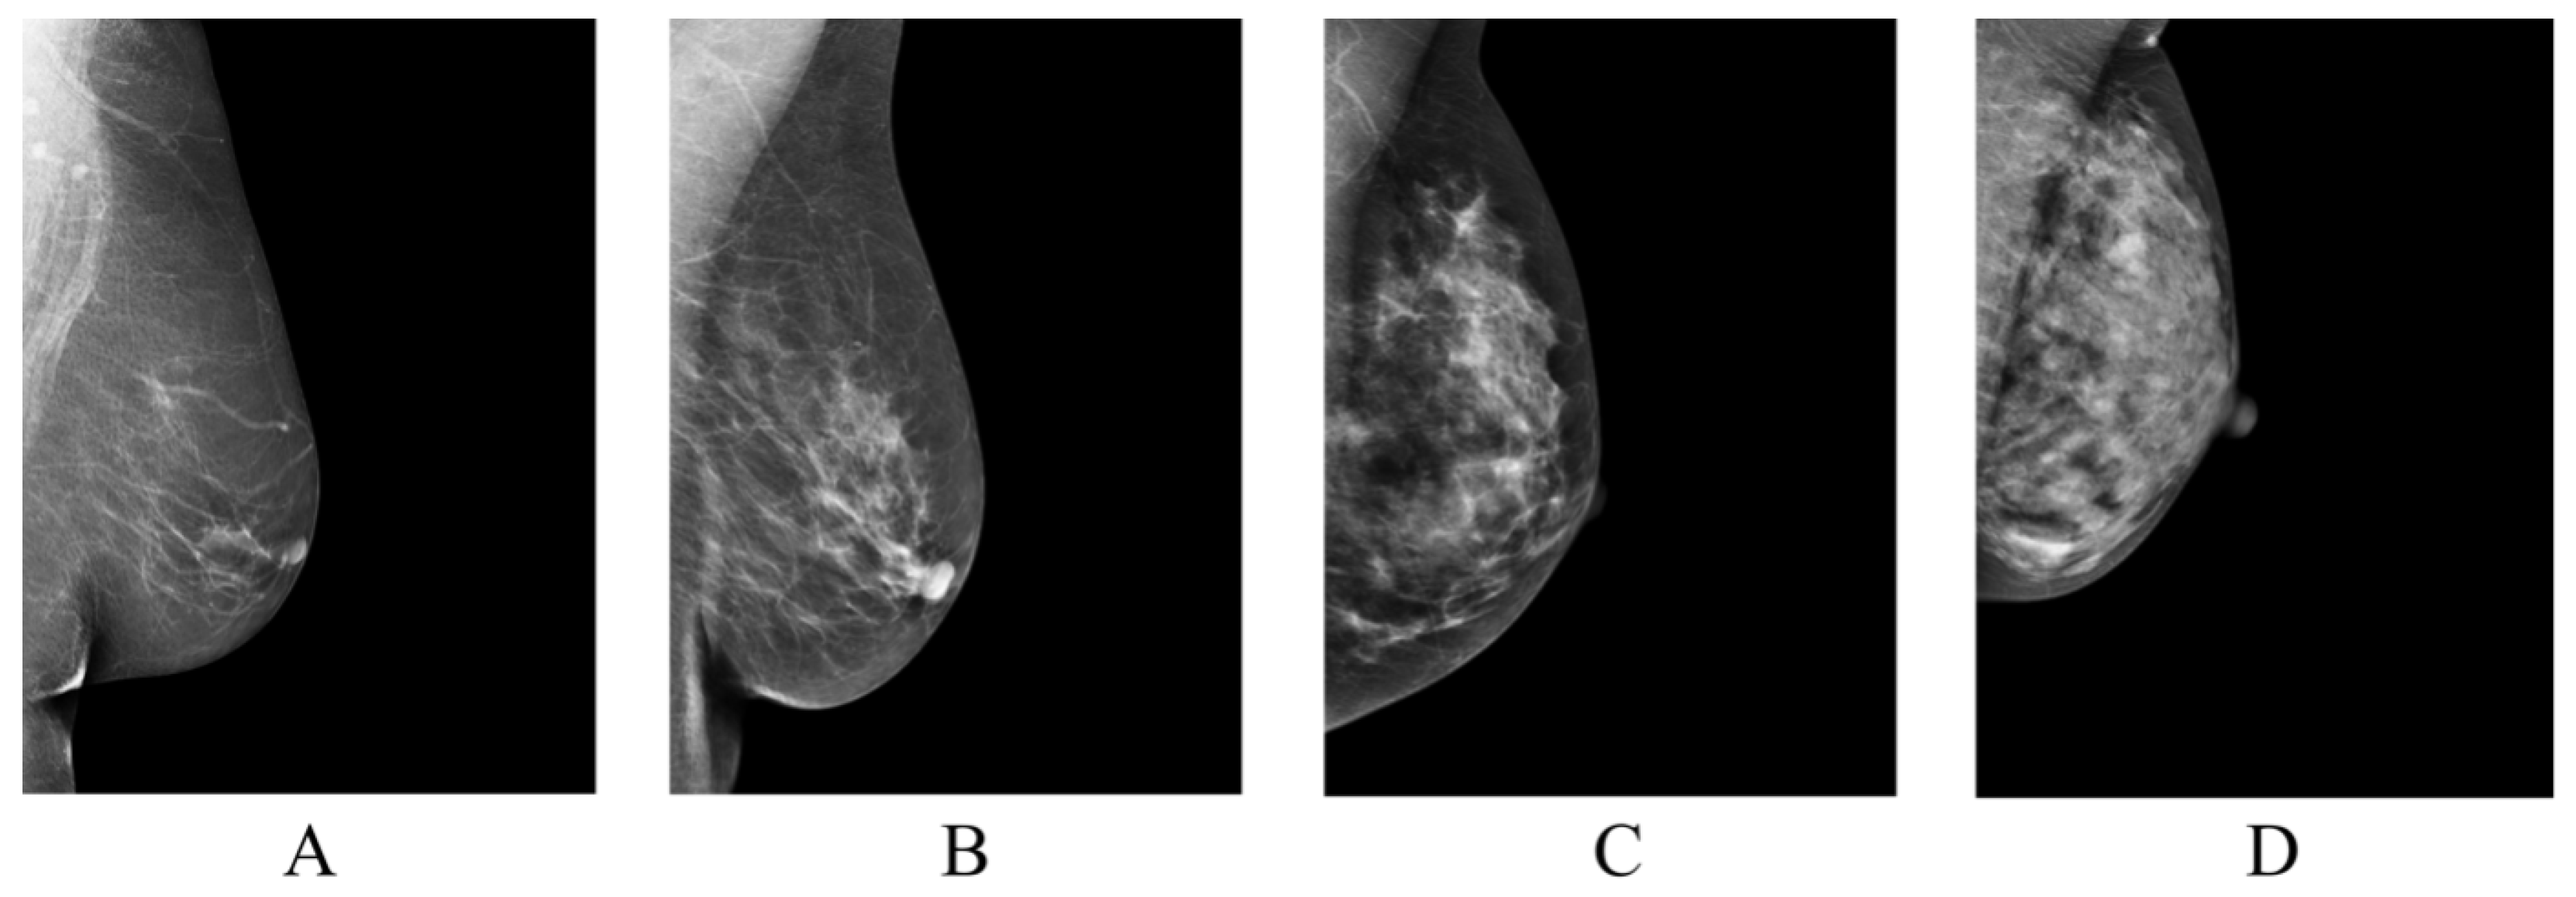

| BI-RADS | Breast Imaging-Reporting and Data System |

| BI-RADS Category | / |

|---|---|

| Class A | 879/3516 |

| Class B | 3212/12,848 |

| Class C | 928/3712 |

| Class D | 111/444 |

| Total | 5130/20,520 |

| Class A | 18/72 |

| Class B | 43/172 |

| Class C | 7/28 |

| Class D | 4/16 |

| Total | 72/288 |